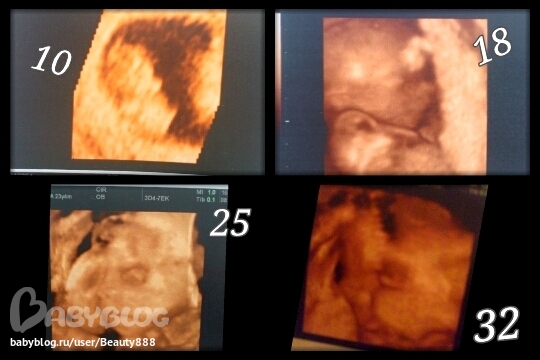

уже большой))) лучше всего видно личико на 18 неделе)))

еще одна есть, но на ней только глаз и маленькую часть носа видно ( в общем, тесно ему там уже... ) да и врач долго ракурс не подбирал. поэтому я даже не знаю, чего посоветовать...

а вообще много хороших снимков получилось? а видео? просто на 15 получилось все здорово, а на 32-34 говорят ничего не понятно